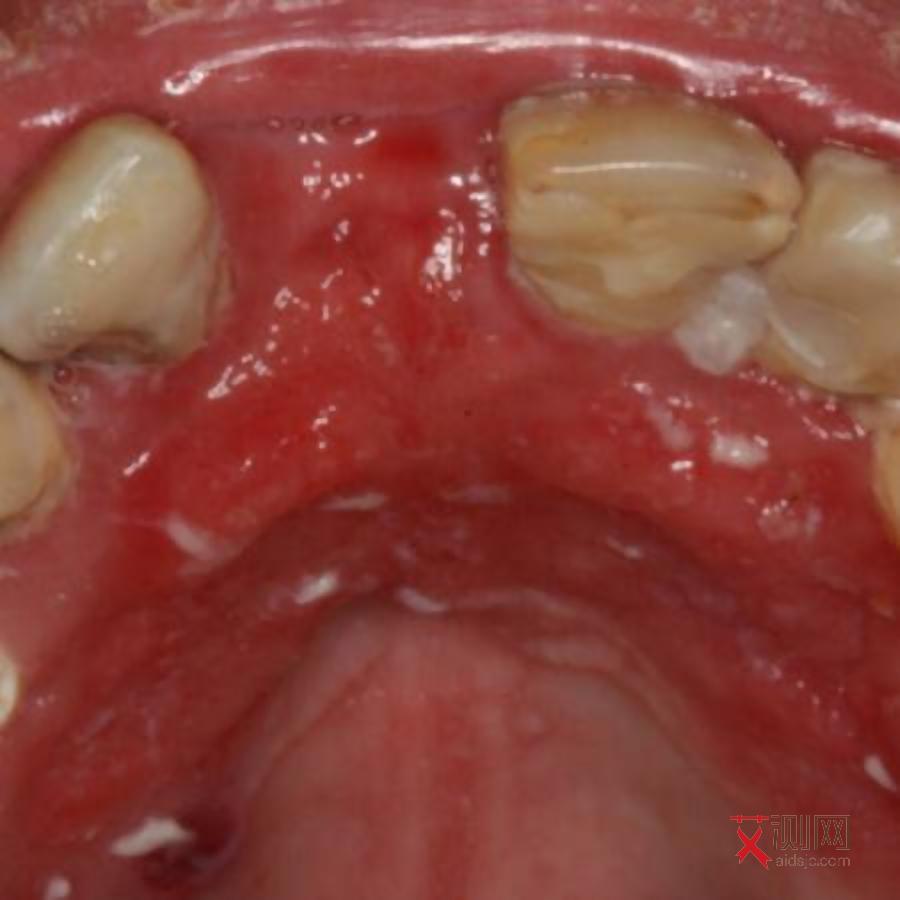

艾滋病初期,也就是急性感染期,通常发生在感染 HIV 后的 2 - 4 周。这个阶段,部分感染者会出现一系列类似感冒的症状,如发热、咽痛、盗汗、呕吐、腹泻、皮疹等。然而,出血点并非艾滋病初期的典型症状。

一般来说,出血点常见于血小板减少或凝血功能异常等情况。在艾滋病初期,虽然病毒在体内大量复制,免疫系统开始受到攻击,但通常不会立即引发严重的血小板减少或凝血障碍,所以出现明显出血点的情况相对少见。不过,这并不意味着完全不可能。个别感染者由于自身免疫系统对病毒反应较为强烈,或者本身存在一些基础疾病,可能会在初期出现轻微的皮肤瘀点、瘀斑等类似出血点的表现,但这种情况较为罕见。如果发现身体出现不明原因的出血点,同时近期有过高危行为,不能排除与艾滋病感染有关,但也不能仅凭这一点就断定感染了艾滋病,还需要结合其他症状和专业的检测来判断。